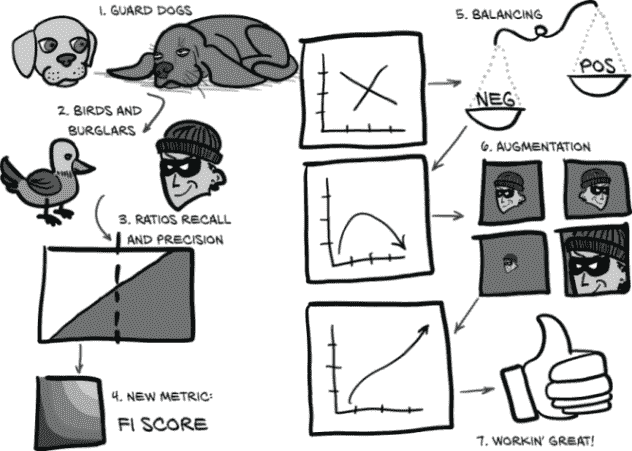

虽然有点抽象,图 12.2 向我们展示了我们将如何处理那些广泛的主题。

让我们详细地走过本章的这张有些抽象的地图。我们将处理我们面临的问题,比如过度关注单一、狭窄的指标以及由此产生的行为在一般意义上是无用的。为了使本章的一些概念更具体化,我们将首先使用一个比喻来将我们的困境更具体化:在图 12.2 中,(1)看门狗和(2)鸟和窃贼。

图 12.2 我们将使用的比喻来修改衡量我们模型的指标,使其变得出色

之后,我们将开发一个图形语言来代表上一章实施中所需的核心概念:(3)比率:召回率和精确率。一旦我们将这些概念巩固下来,我们将涉及一些使用这些概念的数学,这将包括一种更健壮的评估我们模型性能的方式,并将其压缩为一个数字:(4)新指标:F1 分数。我们将实施这些新指标的公式,并查看在训练过程中每个时期这些结果值如何变化。最后,我们将对我们的LunaDataset实现进行一些急需的更改,以改善我们的训练结果:(5)平衡和(6)增强。然后我们将看看这些实验性的更改是否对我们的性能指标产生了预期的影响。

到本章结束时,我们训练的模型将表现得更好:(7)工作得很棒!虽然它还没有准备好立即投入临床使用,但它将能够产生明显优于随机的结果。这意味着我们已经有了可行的第 4 步实现,结节候选分类;一旦完成,我们可以开始考虑如何将第 2 步(分割)和第 3 步(分组)纳入项目中。